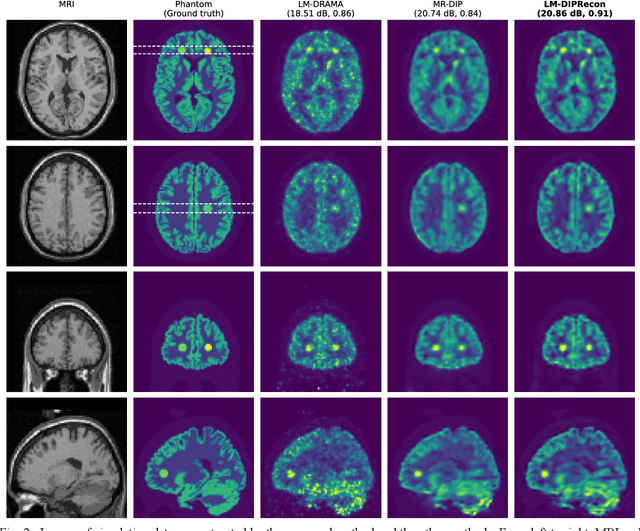

Abstract:List-mode positron emission tomography (PET) image reconstruction is an important tool for PET scanners with many lines-of-response (LORs) and additional information such as time-of-flight and depth-of-interaction. Deep learning is one possible solution to enhance the quality of PET image reconstruction. However, the application of deep learning techniques to list-mode PET image reconstruction have not been progressed because list data is a sequence of bit codes and unsuitable for processing by convolutional neural networks (CNN). In this study, we propose a novel list-mode PET image reconstruction method using an unsupervised CNN called deep image prior (DIP) and a framework of alternating direction method of multipliers. The proposed list-mode DIP reconstruction (LM-DIPRecon) method alternatively iterates regularized list-mode dynamic row action maximum likelihood algorithm (LM-DRAMA) and magnetic resonance imaging conditioned DIP (MR-DIP). We evaluated LM-DIPRecon using both simulation and clinical data, and it achieved sharper images and better tradeoff curves between contrast and noise than the LM-DRAMA and MR-DIP. These results indicated that the LM-DIPRecon is useful for quantitative PET imaging with limited events. In addition, as list data has finer temporal information than dynamic sinograms, list-mode deep image prior reconstruction is expected to be useful for 4D PET imaging and motion correction.